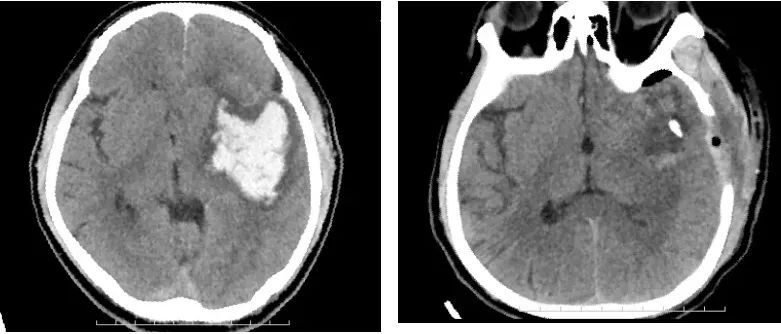

接诊后,医院急诊科迅速联系神经外科医生并立即启动了绿色通道,第一时间对患者进行了全面而精准的检查评估,确诊为高血压脑出血,头部CT报告显示出血量超过了60毫升,病人危在旦夕。

神经外科团队立即为患者实施了颅内血肿清除手术治疗,在急诊科、神经外科、放射科、麻醉科、手术室等相关科室的高效配合下,为患者彻底清除了颅内血块,患者各项功能逐步恢复。经过几天的康复治疗,患者右侧偏瘫和言语障碍也几乎接近正常。

手术之前(左)和手术之后(右)对比